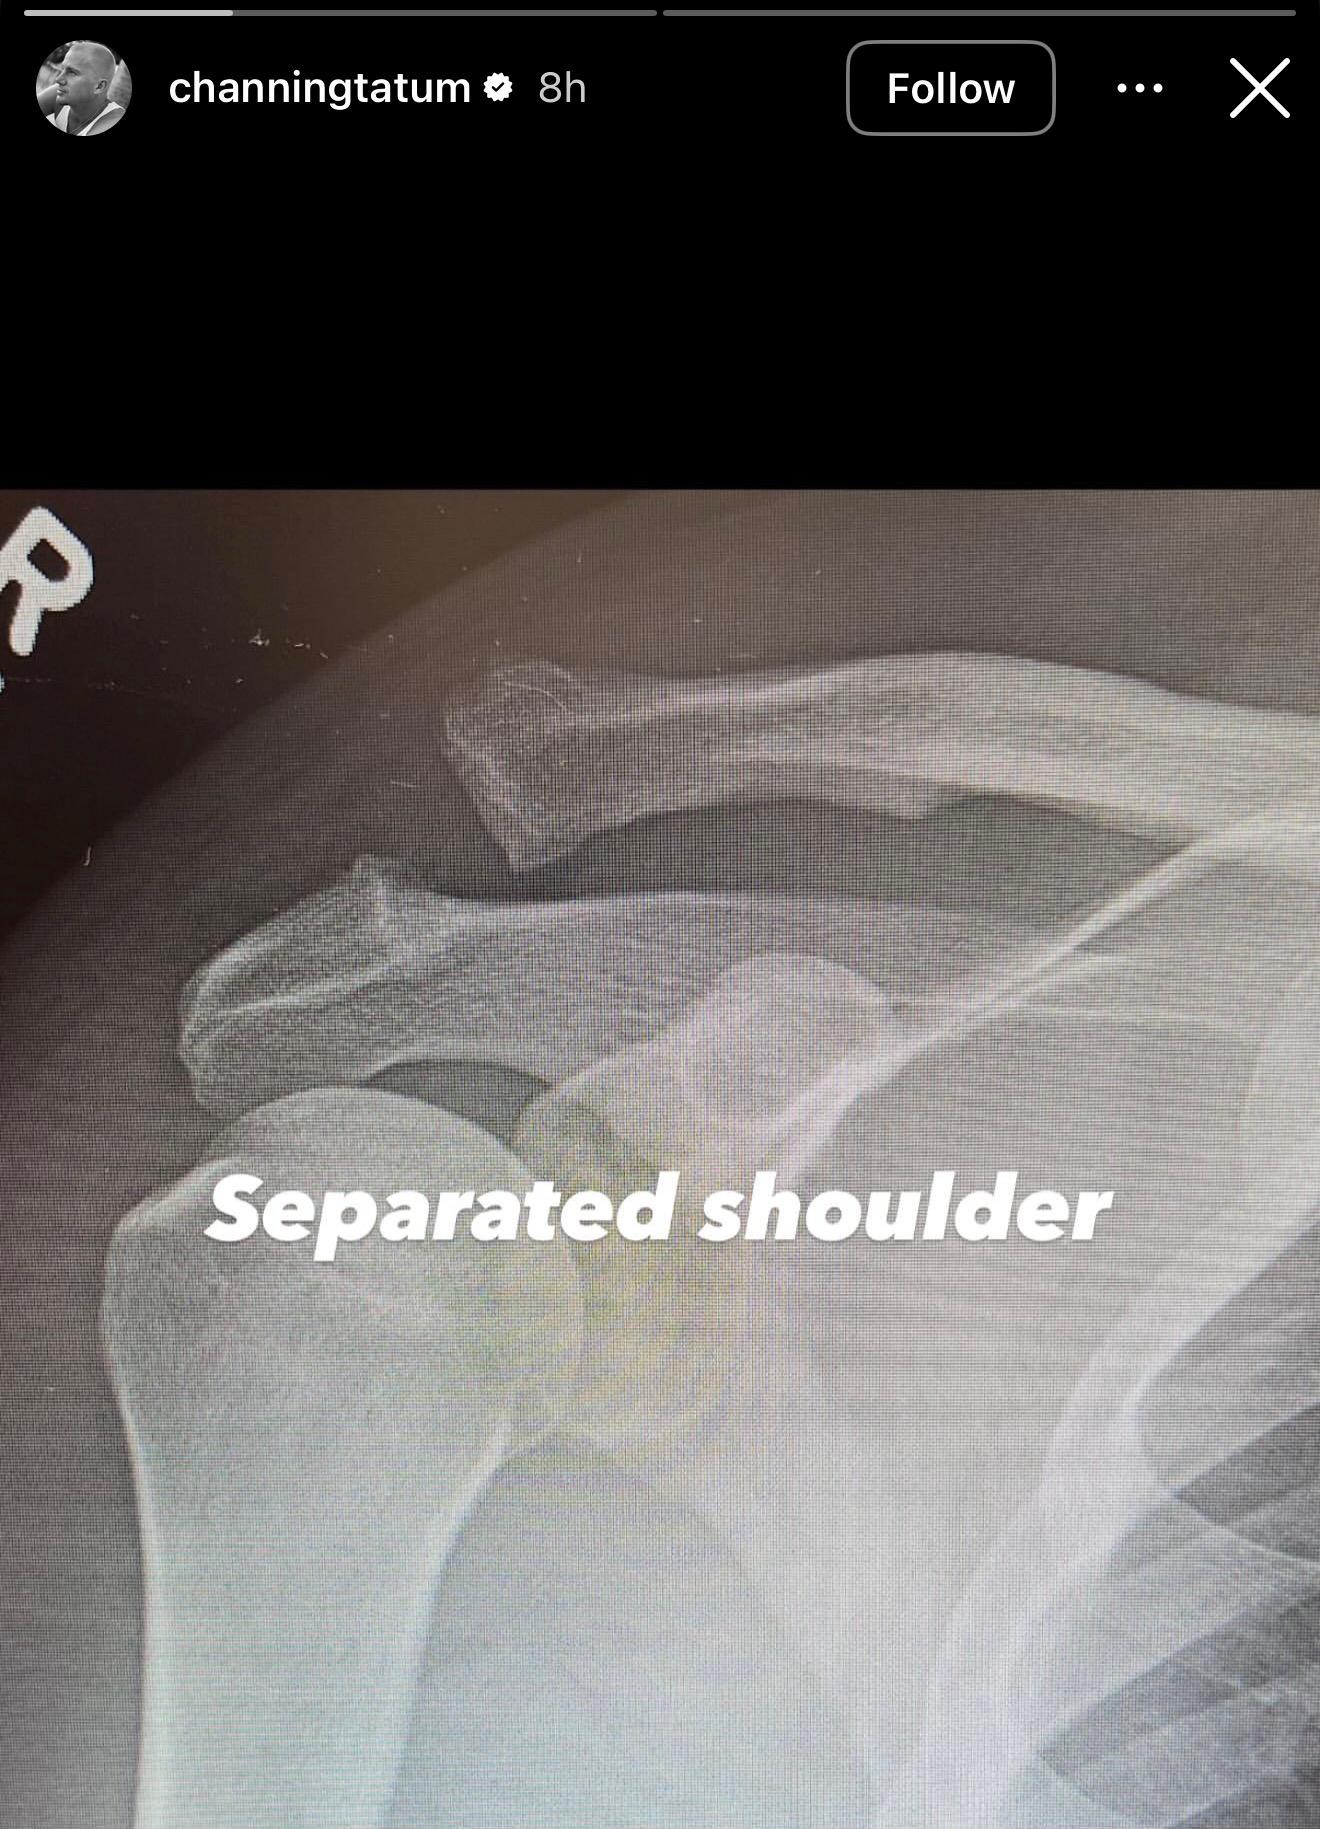

Tatum shared more information about his injury on his Instagram Story, sharing two X-rays. The first revealed the bones in his shoulder had separated, while the second showed a screw holding the bones in place. “Screwed shoulder. Yay,” Tatum sarcastically captioned the update.

Instagram Stories | Channing Tatum